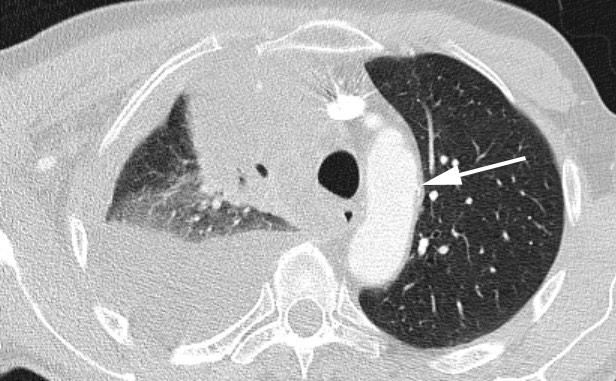

2855. Стрелка на изображении указывает на